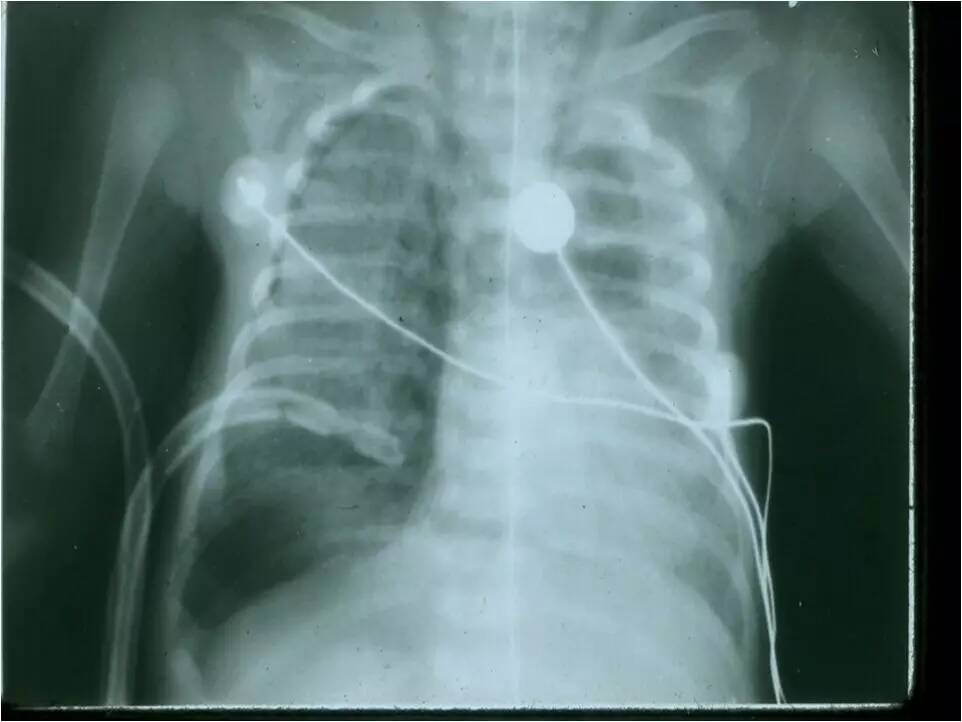

MAS影像学表现

临床特征